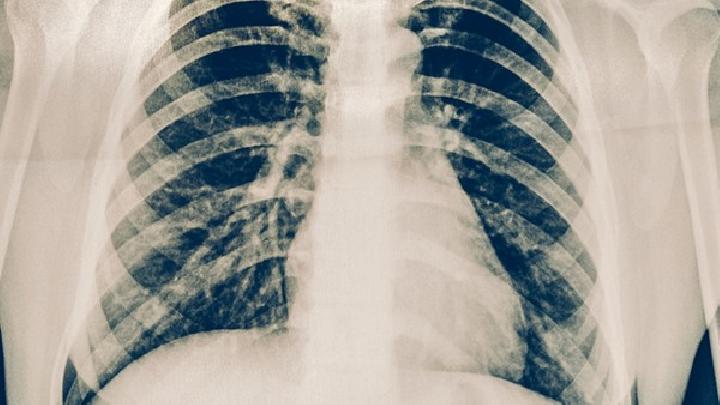

胸部放射检查

胸片的改变包括肺动脉扩张和周围肺纹理减少危重患者中可能有右房,右室的扩大。胸片检查可以帮助排除中到重度的肺部疾病或肺静脉高血压患者。但肺高血压的严重程度和肺部放射性检查的结果并不一致。